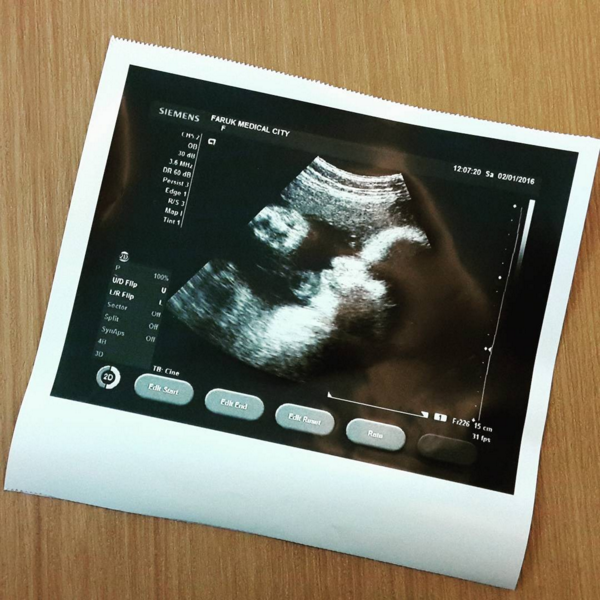

Usg Kehamilan Pada 36 Minggu Cegah Bayi Sungsang

Usg Kehamilan Pada 36 Minggu Cegah Bayi Sungsang

Usg Usia Kehamilan 36 Minggu Sungsang Baby Boy Youtube

Usg Usia Kehamilan 36 Minggu Sungsang Baby Boy Youtube

Gambar Janin Sungsang Caesar Di Usia Kehamilan 36 Minggu

Gambar Janin Sungsang Caesar Di Usia Kehamilan 36 Minggu